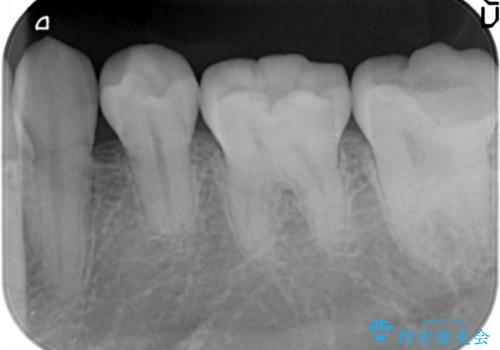

- 左下の7番の虫歯がしみるとのことで来院。

昔他院で虫歯治療した際、「次に虫歯になったらもうきちんとは治せない」と言われたとのことでした。

他院でつめていたものは、セメントで、一時的な詰め物がなされていました。(中は虫歯になっていました。)

虫歯を取ると、歯ぐきの奥深くまで虫歯になっており、そのままではきちんと修復することが難しい状態でした。